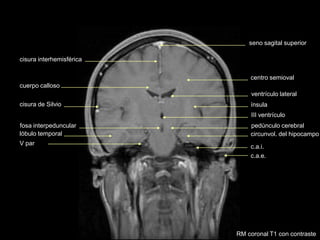

seno sagital superior

cisura de Silvio

lóbulo temporal

cisura interhemisférica

III ventrículo

cuerpo calloso

ventrículo lateral

centro semioval

fosa interpeduncular

ínsula

pedúnculo cerebral

V par

circunvol. del hipocampo

c.a.i.

c.a.e.

RM coronal T1 con contraste